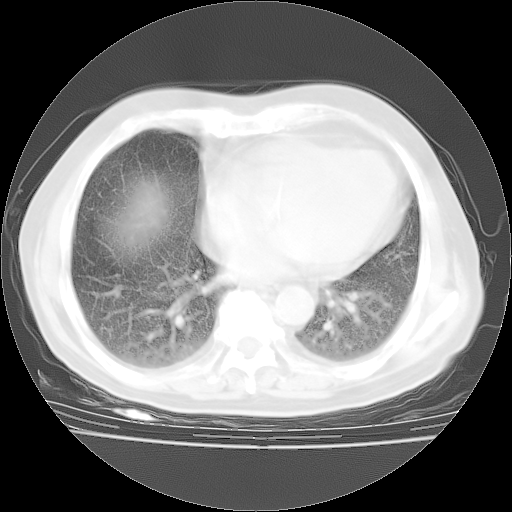

4月28日肺部CT——再次出现类似去年5月9日——透光度降低,“间质性”改变。

4月28日肺部CT——再次出现类似去年5月9日——磨玻璃样、间有“粟粒样”改变。